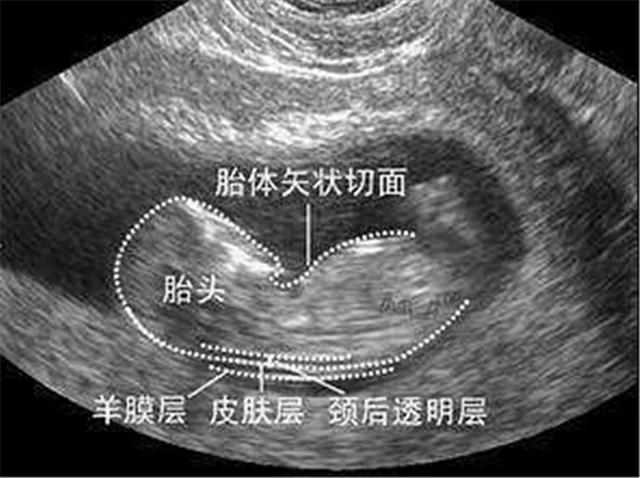

胎儿头脸部

胎儿面部

胎头位于耻骨上,头骨光环光整,脑中线居中,胎儿上唇,鼻骨可预示,生男孩。

胎儿羊水最大深度

47mm,透声性杰出,为男孩。